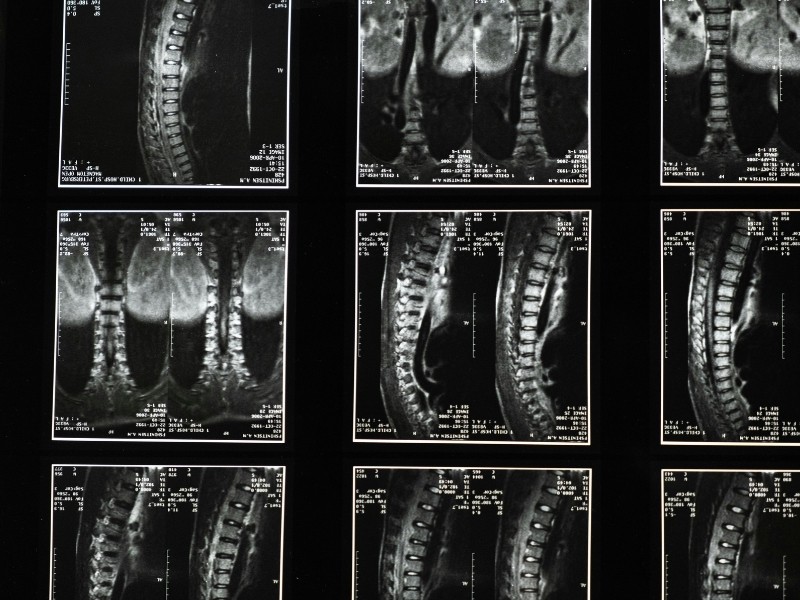

Raio X de Coluna Cervical, Dorsal e Lombo-Sacra em Goiânia – CLIMT SAÚDE A CLIMT SAÚDE realiza Raio X de Coluna Cervical, Dorsal e Lombo-Sacra em Goiânia com tecnologia digital de última geração, oferecendo laudos precisos e atendimento especializado para diagnósticos clínicos e ocupacionais. Desde 1995, somos referência em exames radiológicos de alta confiabilidade, atendendo empresas e pacientes particulares com foco em qualidade, segurança e agilidade. Os exames de coluna são fundamentais para identificar alterações estruturais, degenerativas e traumáticas que comprometem a saúde musculoesquelética do trabalhador ou paciente. Nossos procedimentos seguem padrões técnicos rigorosos, garantindo imagens nítidas, interpretação médica segura e rastreabilidade total dos resultados. Com radiologistas experientes, protocolos baseados nas normas da ANVISA e do Ministério do Trabalho e Emprego (MTE), e arquivamento digital com emissão rápida de laudos, a CLIMT SAÚDE assegura total conformidade legal e técnica em cada exame realizado. Seja para avaliações clínicas, admissionais, periódicas ou de retorno ao trabalho, o Raio X de Coluna Cervical, Dorsal e Lombo-Sacra realizado pela CLIMT SAÚDE garante tranquilidade, precisão e respaldo profissional para empresas e pacientes. 📍 Unidades Setor Aeroporto – Av. República do Líbano, nº 333 Centro – Av. Araguaia, nº 835 📞 Agende agora: (62) 3225-7648 🏢 CLIMT SAÚDE – Excelência em Raio X de Coluna Cervical, Dorsal e Lombo-Sacra em Goiânia e Região Metropolitana.